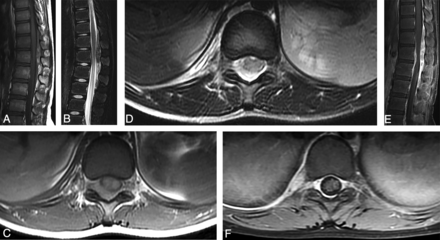

MR imaging of intraspinal paragonimiasis in a 6-year-old patient. Sagittal T1WI (A) and T2WI (B) show a longitudinal fusiform-shaped mass located in the intraspinal extradural space parallel to the level of T2–T11, with predominant isointensity on T1WI and hyperintensity on T2WI, and there are multiple patchlike hemorrhagic areas with hyperintensity on T1WI and hypointensity on T2WI within the mass. Axial T1WI (C) and T2WI (D) show that the mass is located in the extradural space and extends to the right intervertebral foramen, connecting to the irregularly thickened pleural lesions on the right, accompanied by a small amount of pleural effusion. The compressed spinal cord moves slightly to the left front, and there is edema with hyperintensity on T2WI. The sagittal (E) and axial (F) views of the contrast-enhanced images indicate that the mass is obviously enhanced, and there are scattered nonenhancement areas within it. Additionally, the adjacent spinal meninges show obvious enhancement.

The plain MR imaging scan of the 6 granulomatous lesions showed mixed signals with predominant isointensity on T1WI (Figs 1A, -C and 2A, -C) and hyperintensity on T2WI (Figs 1B, -D and 2B, -D), of which 5 fusiform-shaped lesions presented with multiple patchlike or irregular hemorrhagic foci with hyperintensity on T1WI within the masses (Figs 1A, -C and 2A, -C). The 5 patients undergoing the enhanced MR image showed heterogeneous and marked enhancement in the granulomatous masses (Figs 1E, -F and 2E, -F). The lesions in the intervertebral foramen and the pleura showed an enhancement pattern that was similar to that in the intraspinal lesions (Figs 1F and 2F). Furthermore, there was enhancement in the adjacent spinal meninges (Figs 1E and 2E).

In 5 of the 6 patients, the corresponding segment of the spinal cord exhibited various degrees of compression and edema, which was visible as hyperintensity on T2WI (Fig 1B, -D).